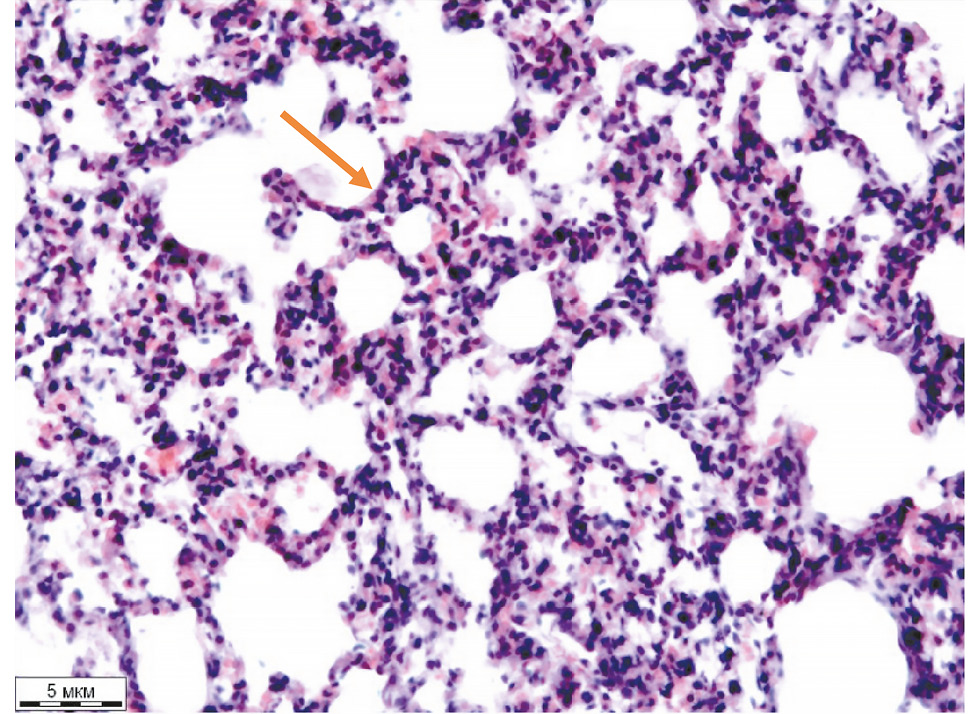

Через 3 часа после введения баклофена мы отмечали деформацию бронхиол, значительные нарушения микроциркуляции (венозное и капиллярное полнокровие, появление единичных кровоизлияний в МАП), наличие ателектазов и дистелектазов, чередовавшихся с участками эмфиземы. Отмечали также значительное утолщение МАП за счёт полнокровия капилляров, кровоизлияний и пропитывания серозной жидкостью. Перибронхиальная и периваскулярная соединительная ткань была отёчна. На участках МАП, в венулах, посткапиллярах наблюдали скопление сегментоядерных лейкоцитов (рис. 1).

Рис. 1. Лёгкое крысы (баклофен, 3 часа): утолщение межальвеолярных перегородок и их инфильтрация сегментоядерными лейкоцитами (стрелка). Окраска гематоксилином-эозином, ×200.

Fig. 1. Rat lung (baclofen, 3 hours): thickening of the interalveolar septa and their infiltration by segmented leukocytes (arrow). Hematoxylin and eosin staining, ×200.